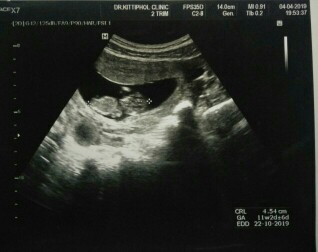

มาอวดภาพแรกของเจ้าตัวน้อยกันคะ

อยากเห็นภาพแรกของเจ้าตัวน้อย. ของแม่ๆ. แต่ละบ้านบ้างอะคะ. มาแชร์ประสบการณ์กันได้นะคะ❤️

ตอน 11 W คะ